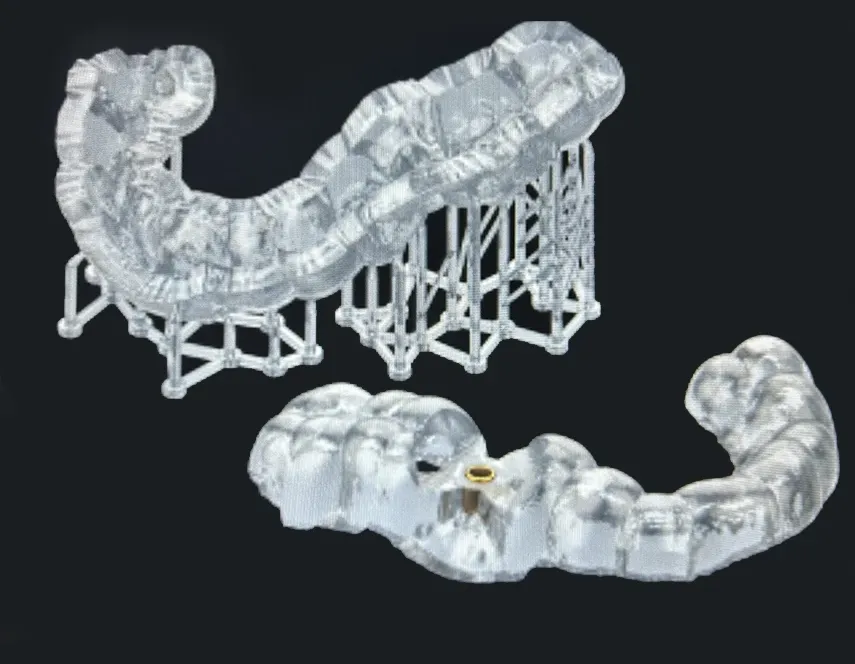

Flujo digital clínico

Implementamos flujo digital completo con CAD/CAM e impresión 3D profesional, optimizando cada etapa del caso para lograr mayor precisión, mejor ajuste desde la primera prueba y tiempos de entrega controlados.

Soluciones implantológicas

Férulas y dispositivos digitales